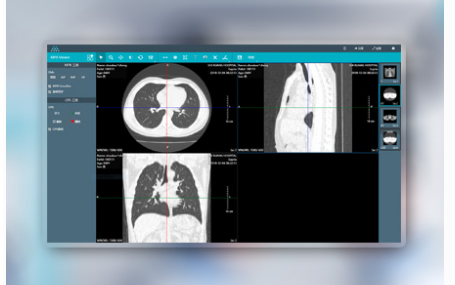

云胶片的便利性有哪些?云PACS/医共体软件迈德卫医疗影像云告诉你!云胶片的便利性有哪些呢?我们都知道云胶片给医生和患者带来的极大的便利性,它给我们带来什么变化呢?跟着云PACS/医共体软件迈德卫医疗影像云一起了解下吧!首先云胶片的便利性体现在它的即时调阅,医生和患者可以随时查看影像资料!它还可以生成二维码图片,可以直接要我们的微信扫码进入查看。云胶片还可以分享下载...

和传统胶片说再见,云胶片来啦!远程超声/远程会诊迈德卫医疗影像云关于云胶片的那些事!以往,去过医院做过检查的人都知道,检查过后,需要在医院等待胶片的出来!有的还需要去排队领取,费时间还比较麻烦!现在云胶片来啦,告别排队领取的烦恼!跟着远程超声/远程会诊迈德卫医疗影像云一起了解下吧!我们现在使用的云胶片,它除了具备传统胶片的各项功能,而且还能实现影像资料云端浏览、下载、异地打印等功能...